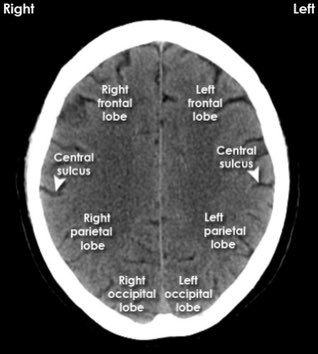

▫️نبدأ بأشعة مقطعية طبيعية للرأس

Normal Head CT scan

▫️صور تشريحية جدا رائعة 🧠🌟